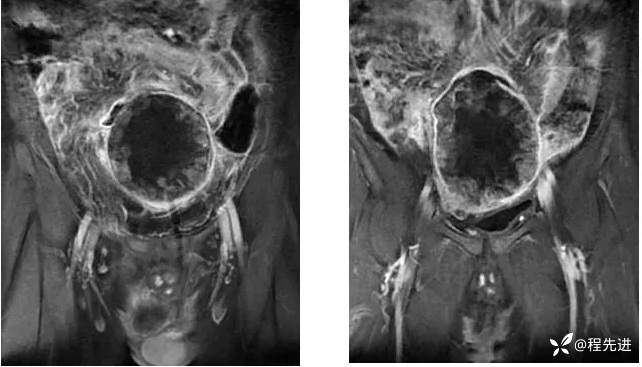

【患者信息】:男,41岁

【主诉】:下腹痛20余天

【现病史及既往史】:患者20余天前无明显诱因下出现下腹部疼痛,呈阵发性闷痛,无恶心,无呕吐,无腹泻,无尿频、尿急,无黄疽,无发热、畏寒,无胸闷、气促,一直未予就诊,症状反复发作,今为进一步诊治,于外院行相关检查后,到我院就诊,门诊拟“盆腔包块"收入本科。起病以来,患者精神、胃纳、睡眠好,大小便正常。

既往史:隐睾

肿瘤标志物:甲胎蛋白(AFP)>10000

增强: